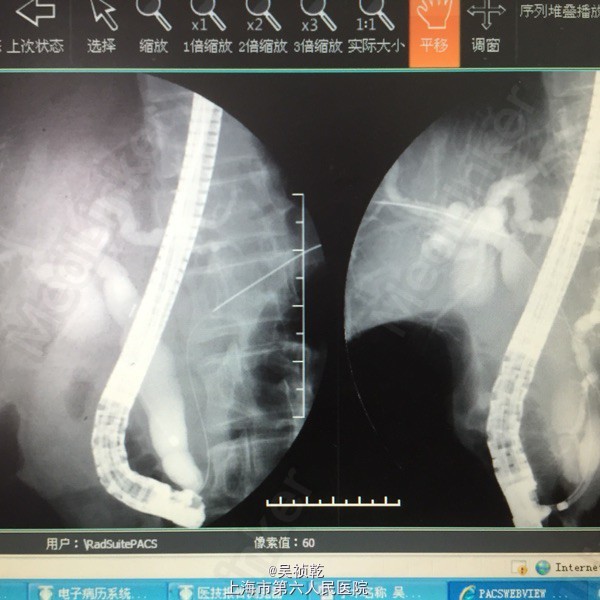

1. 患者入院后于4.13无明显诱因下出现右上腹疼痛,压痛明显,拒按。结合腹部CT及MRI影像学表现,胰胆管明显扩张,考虑急性胰腺炎发作。辅查:2015-4-14 生化检验报告:淀粉酶(干式) 1640 U/L ↑。生化检验报告:总蛋白 61 g/L ,白蛋白 36 g/L ,白/球比例 1.4 ,谷丙转氨酶 218 U/L ↑,谷草转氨酶 183 U/L ↑,γ-谷氨酰酶 548 U/L ↑,总胆红素 13.3 μmol/L ,直接胆红素 5.4 μmol/L ,肌酐 66 μmol/L ,血清钾 4.3 mmol/L ,血清钠 142 mmol/L ,血清氯 106 mmol/L ↑。门诊化验检验报告:白细胞 6.3 *10^9/L ,红细胞 3.84 X10^12/L ,血红蛋白 117 g/L ,细胞比积 35.9 % ,血小板 197 X10^9/L ,中性细胞百分比 58.7 % 。甲胎蛋白(AFP) 2.68 ng/mL ,癌胚抗原(CEA) 4.99 ng/mL ,糖类抗原(CA125) 6.91 U/mL ,糖类抗原(CA199) 39.45 U/mL ↑。处理:予禁食,查血、尿淀粉酶,抑酸、保肝、补液支持治疗,经治疗后症状缓解。 2. 因患者无黄疸,为进一步明确胆总管梗阻原因,4.16 行ERCP+ERBD+十二指肠乳头活检术。 检查治疗经过:十二指肠镜进入十二指肠,降部内侧见乳头,十二指肠乳头肿大,粘膜面外观正常,触之易出血。BOSTON-Jagwire导丝留置胰管,BOSTON-Jagwire导丝进入胆管引导COOK-FS-OMNI导管造影,胆管显影,胆管扩张,胰管造影胰管扩张。胆管胰管内未见充盈缺损。十二指肠乳头开口处取四块活检。放置辛菖猪胆道引流管(8.5F,6cm),辛菖胰管引流(F5,4cm),引流畅。结合MRI及CT考虑壶腹部占位可能。十二指肠乳头活检病理:绒毛状腺瘤伴部分腺体重度不典型增生,局灶癌变。 3. 患者术前诊断为十二指肠壶腹部癌,于4.23 行剖腹探查,胰十二指肠切除术。术中见:见腹腔内无腹水,腹膜、盆腔内、大网膜、肝脏、肝十二指肠韧带、胰腺周围、腹腔动脉周围、肠系膜根部、腹主动脉旁等无转移性结节和肿大淋巴结。探查见此患者左右肝胆管的汇合处接近胆胰管汇合处,右侧肝胆管壁水肿增粗,十二指肠乳头部肿块大小0.3cm,行胰十二指肠完整切除。 4. 术后病理检查报告:下半胃、胰腺、十二指肠;标本类型:切除胰腺大小 4×4×1 CM,十二指肠长 15CM,胃小弯长 8 CM,大弯长 11CM,胆囊9×3×1.5CM;肿瘤部位:肿瘤位于十二指肠乳头,大小0.5×0.3CM;组织学类型内容: 腺癌II级;血管浸润(-),淋巴管浸润(-),神经周围浸润(-);切缘: 上、下切缘及胰腺切缘均未见癌;淋巴结:以下淋巴结均未见癌转移:胰腺旁LN:0/8枚,胃大弯LN:0/6枚,胃小弯LN:0/3枚。;淋巴结免疫反应状态: SH(+), PH(+), GH(+);肿瘤旁病变: 粘膜组织慢性炎(十二指肠乳头):腺癌II级,肿瘤侵及肌层,未累及胰腺,胰腺导管扩张,小胆管增生伴中度不典型增生。(胆囊):慢性胆囊炎伴腺体增生。肿瘤组织免疫酶标记结果:CA199(-)、CEA(+)、S-100(-)、CK19(+)、CK7(+)、CDX2(-)、CK(-)、Ki67(80%+)。